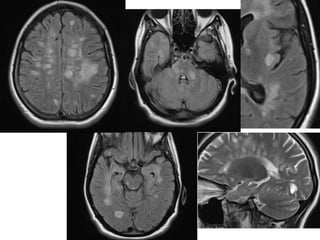

Sagittal T2 fast spin echo images of the

cervical (A, B) and thoracic (C) spine showing

continuous long-segment linear T2 signal

hyperintensity (arrows) involving the spinal

cord extending from the cervicomedullary

junction to the T8-9 level with predominantly

central involvement of the cord in a patient

with neuromyelitis optica

Sagittal T2 fastspin echo images of the cervical (A, B) and thoracic (C) spine showing continuous long-segment linear T2 signal hyperintensity (arrows) involving the spinal cord extending from the cervicomedullary junction to the T8-9 level with predominantly central involvement of the cord in a patient with neuromyelitis optica

Axial T2 fastspin echo (A, B) and sagittal short tau inversion recovery (STIR) (C) sequences showing the typical peripheral signal changes on axial images (A, B) and discontinuous high T2 signal (arrows) involving short segments of the spinal cord (C) in a patient with multiple sclerosis